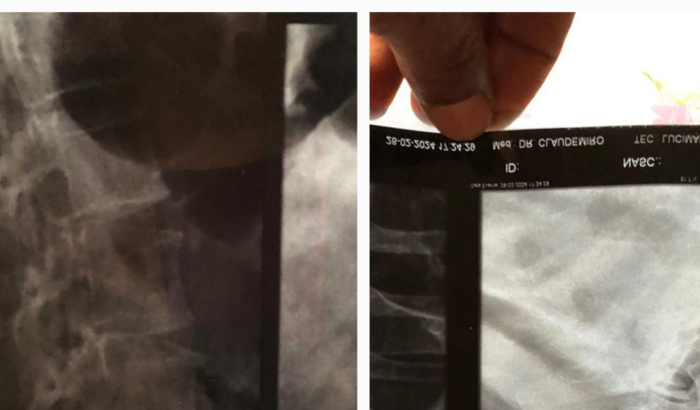

Ola me chamo  Andrea Maria Pifer da Silva em 2018 descobri que tenho um problema coluna que chama Discoplatia degenerativa onde em 2019 fiz um cirrugia mais sem condicoes nao cosegui continuar meu tratamento ate porque meu tratamento e car ver tudo

• Ola me chamo  Andrea Maria Pifer da Silva em 2018 descobri que tenho um problema coluna que chama Discoplatia degenerativa onde em 2019 fiz um cirrugia mais sem condicoes nao cosegui continuar meu tratamento ate porque meu tratamento e caro fica en torno so de remedio o valor de 3.680  mes e a renda do meu esposo e de 2.700 mes entao ou comemos ou pagamos o remedio  e sem conseguir  ajuda dos orgao publico eu venho encarecidamente tentar ajuda de quem se solidarizar com minha historia

• Pois tenho que retomar meu tratamento onde tenho que fazer exames de auto custo consultas com neuro e ortopedista e agora duas  cirugia uma no pescoço e outra na coluna logo apos terei que fazer fizioterapia onde terei que tomar tambem remedios  e terei que voltar a retornos medico ja que moro na cidade de Sonora MS e me trato em APARECIDA DE GOIANIA G hoje tenho que operar o pecoco e a coluna venho pedir quem poder ajudar agradeco de todo coracao pois nao aguento mais sentir dor 24 horas nao ter mais qualidade de vida tem horas que penso em desistir pois as dores sao muito forte desde ja agradeco de todo meu coracao se preferir ajudar no pix deiapifer2@gmail.com